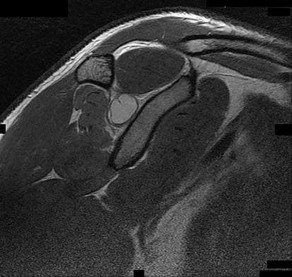

A 55-year-old man presents with an insidious onset of dull, aching shoulder pain. Radiographs demonstrate a calcified intramedullary lesion in the proximal humerus with endosteal scalloping involving 80% of the cortical thickness. Biopsy confirms a low-grade chondrosarcoma. What is the most appropriate definitive management?

Correct Answer: Wide surgical resection with anatomic reconstruction

Explanation:

The clinical and radiographic presentation is classic for a primary central chondrosarcoma. Unlike enchondromas, chondrosarcomas frequently exhibit endosteal scalloping greater than 2/3 of the cortical thickness and present with mechanical or biologic pain. Chondrosarcomas are notoriously resistant to both chemotherapy and radiation therapy. The mainstay of treatment for conventional chondrosarcoma is wide surgical resection. While extended intralesional curettage may be considered for some appendicular atypical cartilaginous tumors (Grade 1), wide resection is the gold standard, especially with significant endosteal scalloping and risk of cortical breakthrough.